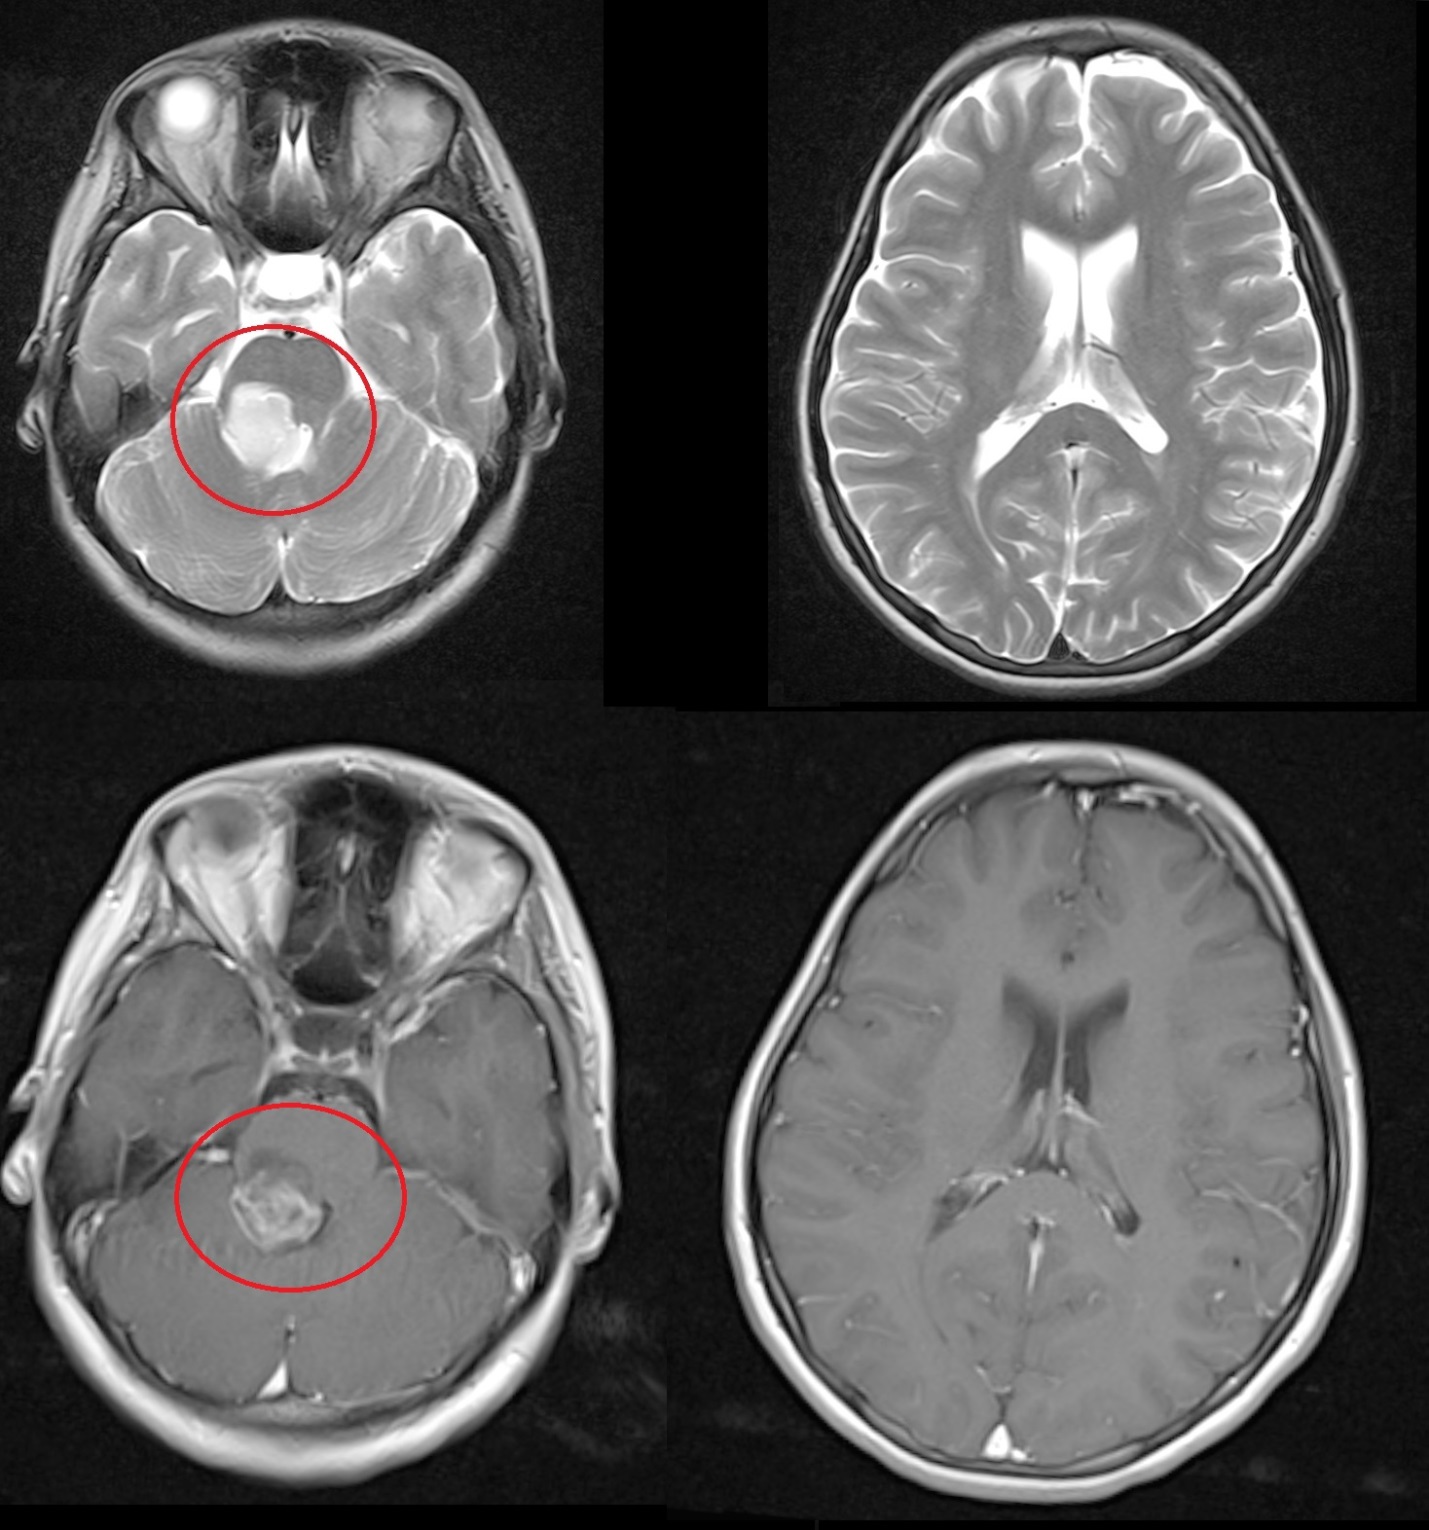

Результаты. У 19 пациентов (50 % от 38 прошедших биопсию) по данным иммуногистохимического анализа послеоперационного материала была выявлена мутация К27М в гене H3F3A. У 6 (15 %) пациентов из 38 МРТ в сроки от 2 до 5 мес (медиана – 4,5 мес) после окончания лучевой терапии выявлено нехарактерное прогрессирование ДСГ в виде метастазирования по желудочковой системе головного мозга. У остальных пациентов когорты исследования, не проходивших процедуру биопсии, подобный характер прогрессирования не наблюдался (p<0,002): у них, как правило, отмечался продолженный рост опухоли (n=96), у 4 больных диагностировано лептоменингеальное метастазирование по спинному мозгу.

Заключение. Нами выявлены случаи нетипичного прогрессирования ДСГ в виде метастазирования по желудочковой системе у детей после открытой биопсии опухоли. Есть основания полагать, что биопсия могла способствовать диссеминации ДСГ по ликворным пространствам. Необходим поиск альтернативных методов оценки молекулярно-генетических характеристик ДСГ.